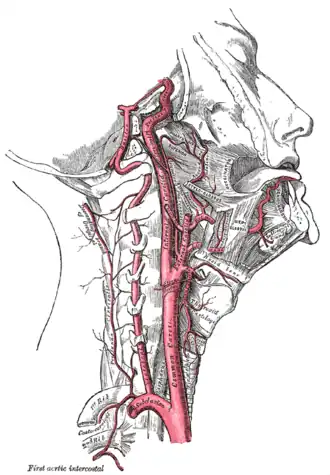

Les artères carotides sont les deux artères carotides communes qui se divisent chacune en une artère carotide interne et une artère carotide externe. Parmi ces deux artères, seule la carotide interne est à destination du cerveau, et elle constitue également sa principale source de vascularisation[1]. La sténose carotidienne peut être de nature athéromateuse ou radique.

La sténose carotidienne est une localisation classique de l'athérome consistant en une infiltration de l'intima de l'artère par des lipides et des cellules. Les facteurs de risque sont ceux de l'athérome : hérédité, sexe masculin, âge, tabagisme, hypertension artérielle, diabète, dyslipidémie. Le plus souvent, la sténose est située au niveau de la bifurcation carotidienne (partie terminale de la carotide commune) ou au niveau de la partie initiale de la carotide interne[2].